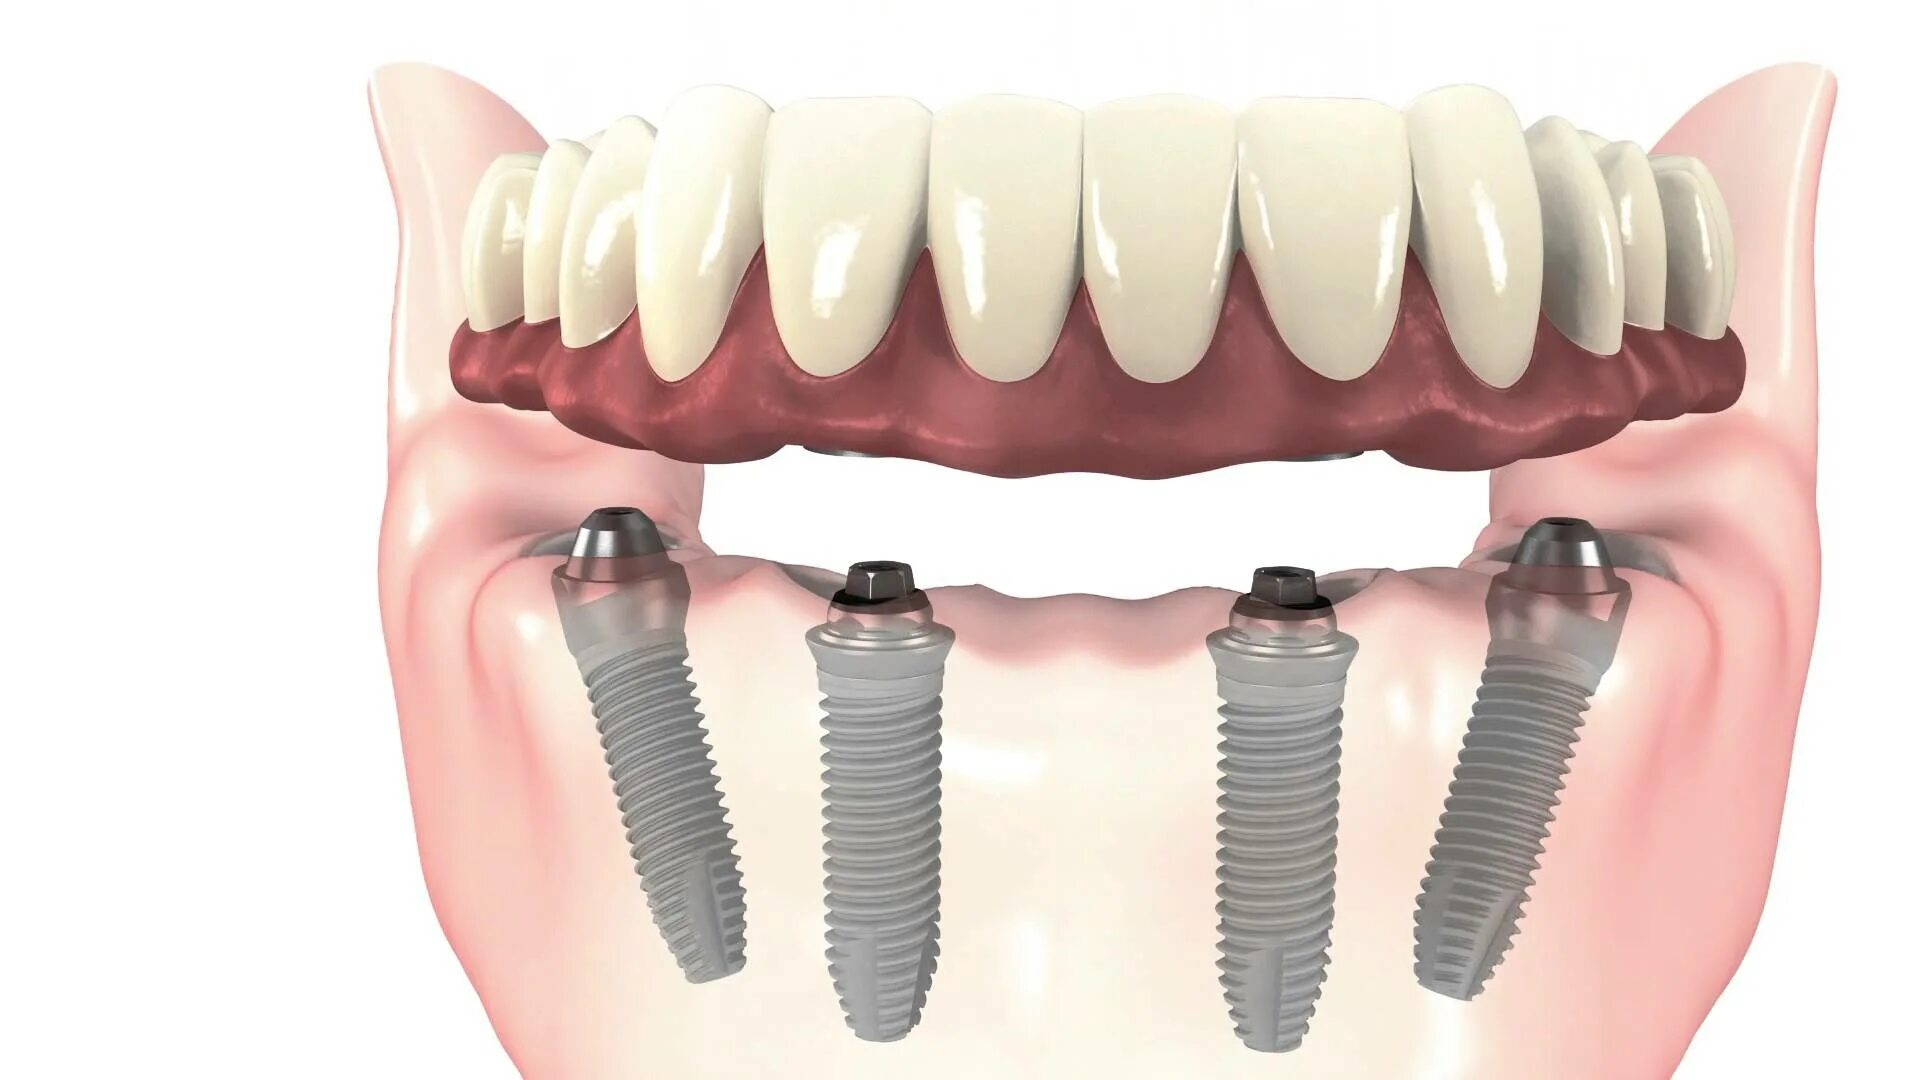

All in установка